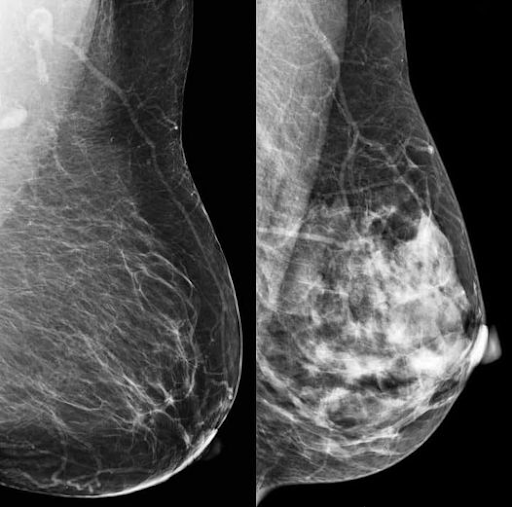

කලින් ලිපියේ කිව්වා පියයුරු වල සම්බන්ධක පටක ගැන. මීට අමතරව මේද අම්ල පටකත් තියෙනවා. සම්බන්ධක පටක ප්රමාණය වැඩි වෙන්න පියයුරු පිළිකා ඇති වීමේ ප්රවණතාවය වැඩි කරනවා. රුපය බලන්න. එක රුපයක් සම්බන්ධක පටක වැඩි සහ අනෙක මේද අම්ල පටක වැඩි උදාහරණ දෙකක්. නමුත් මේ උදාහරණ දෙකම සාමාන්යයයි. නිරෝගියි.